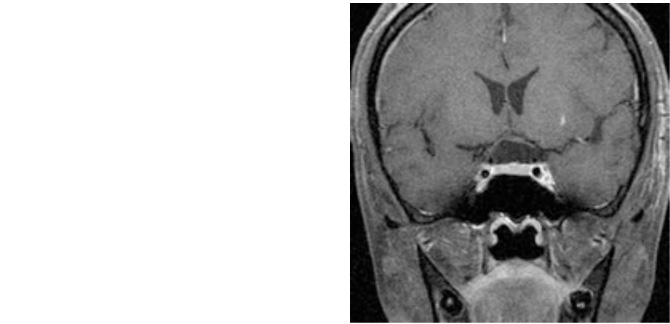

症例1

症例1は急激に進行する視力障害で来院された44歳女性です。視野検査で両目の外側が見えにくい両耳側半盲、右視力1.0、左視力は0.5と低下していました。両側の前頭葉の間から腫瘍を摘出し、視力は術後右1.5、左0.9、視野も改善しました。

図1:視神経を圧迫し視力・視野障害で来院。

術後MRI:腫瘍は摘出され視力も改善し退院。

嗅覚障害出現したが軽快しつつある。